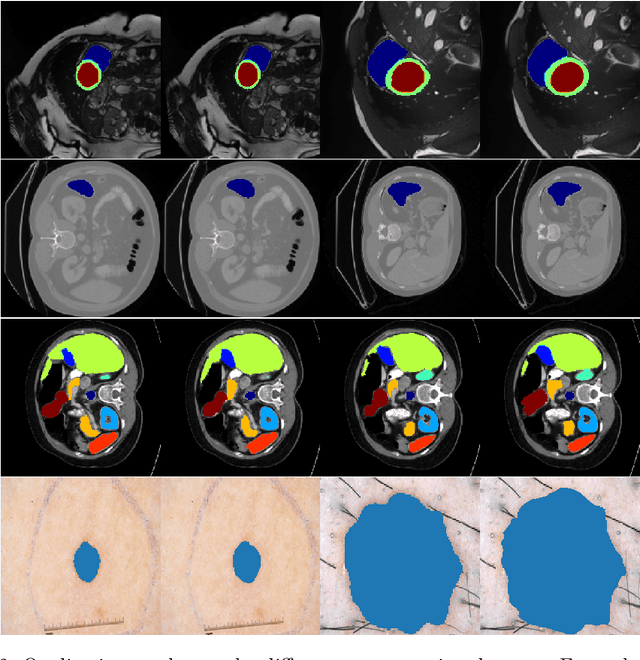

Abstract:We propose a novel transformer-style architecture called Global-Local Filter Network (GLFNet) for medical image segmentation and demonstrate its state-of-the-art performance. We replace the self-attention mechanism with a combination of global-local filter blocks to optimize model efficiency. The global filters extract features from the whole feature map whereas the local filters are being adaptively created as 4x4 patches of the same feature map and add restricted scale information. In particular, the feature extraction takes place in the frequency domain rather than the commonly used spatial (image) domain to facilitate faster computations. The fusion of information from both spatial and frequency spaces creates an efficient model with regards to complexity, required data and performance. We test GLFNet on three benchmark datasets achieving state-of-the-art performance on all of them while being almost twice as efficient in terms of GFLOP operations.

Abstract:We propose a novel transformer model, capable of segmenting medical images of varying modalities. Challenges posed by the fine grained nature of medical image analysis mean that the adaptation of the transformer for their analysis is still at nascent stages. The overwhelming success of the UNet lay in its ability to appreciate the fine-grained nature of the segmentation task, an ability which existing transformer based models do not currently posses. To address this shortcoming, we propose The Fully Convolutional Transformer (FCT), which builds on the proven ability of Convolutional Neural Networks to learn effective image representations, and combines them with the ability of Transformers to effectively capture long-term dependencies in its inputs. The FCT is the first fully convolutional Transformer model in medical imaging literature. It processes its input in two stages, where first, it learns to extract long range semantic dependencies from the input image, and then learns to capture hierarchical global attributes from the features. FCT is compact, accurate and robust. Our results show that it outperforms all existing transformer architectures by large margins across multiple medical image segmentation datasets of varying data modalities without the need for any pre-training. FCT outperforms its immediate competitor on the ACDC dataset by 1.3%, on the Synapse dataset by 4.4%, on the Spleen dataset by 1.2% and on ISIC 2017 dataset by 1.1% on the dice metric, with up to five times fewer parameters. Our code, environments and models will be available via GitHub.